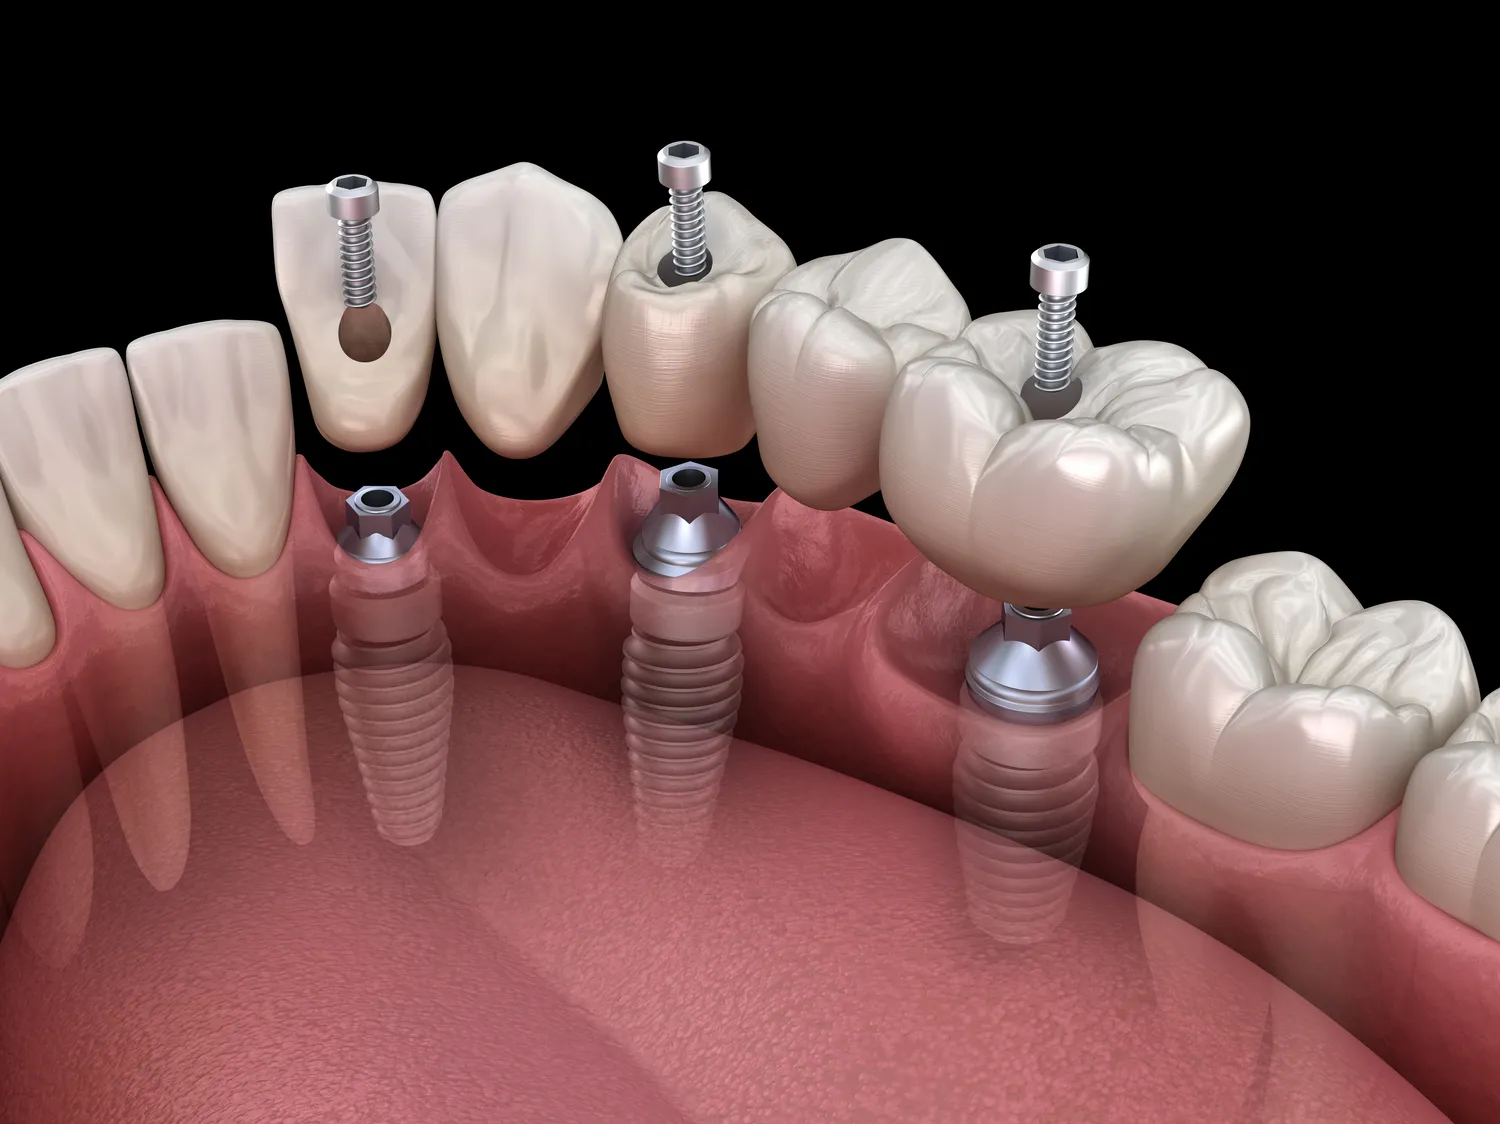

Proces zakupu implantów w jeden dzień w Kołobrzegu rozpoczyna się od konsultacji ze specjalistą, który oceni stan uzębienia pacjenta oraz zaproponuje odpowiednie rozwiązania. Na tym etapie lekarz przeprowadza dokładne badania diagnostyczne, takie jak zdjęcia rentgenowskie czy tomografia komputerowa, które pozwalają na precyzyjne zaplanowanie zabiegu. Po ustaleniu planu działania pacjent jest informowany o wszystkich krokach oraz kosztach związanych z procedurą. Następnie następuje etap przygotowawczy, który obejmuje ewentualne leczenie kanałowe lub usunięcie zębów, jeśli to konieczne. W dniu zabiegu lekarz przeprowadza implantację zgodnie z wcześniej ustalonym planem. Dzięki zastosowaniu znieczulenia miejscowego pacjent nie odczuwa bólu ani dyskomfortu podczas całej procedury. Po umieszczeniu implantu lekarz przystępuje do mocowania korony protetycznej, co sprawia, że pacjent może wyjść z gabinetu z nowym uśmiechem już tego samego dnia.

Najnowsze technologie stosowane w implantach w jeden dzień w Kołobrzegu znacząco poprawiają jakość i efektywność leczenia. Jednym z kluczowych osiągnięć jest zastosowanie cyfrowych technologii obrazowania oraz planowania zabiegów. Dzięki tomografii komputerowej lekarze mogą dokładnie ocenić anatomię szczęki pacjenta oraz precyzyjnie zaplanować umiejscowienie implantu. To znacznie zwiększa szanse na sukces całej procedury oraz minimalizuje ryzyko powikłań. Kolejnym innowacyjnym rozwiązaniem jest wykorzystanie systemów CAD/CAM do produkcji koron protetycznych. Dzięki tym technologiom możliwe jest szybkie i precyzyjne wykonanie korony, co pozwala na jej zamocowanie jeszcze tego samego dnia. Warto również wspomnieć o nowoczesnych materiałach stosowanych do produkcji implantów, takich jak tytan czy ceramika, które charakteryzują się wysoką biokompatybilnością oraz trwałością. Dodatkowo, niektóre kliniki stosują techniki augmentacji kości, które umożliwiają przeprowadzenie zabiegu nawet u pacjentów z niedostateczną ilością tkanki kostnej.